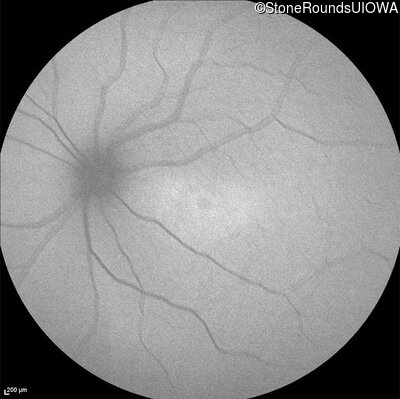

Age at visit: 16 years

Age at visit: 17 years

Age at visit: 18 years

Age at visit: 22 years